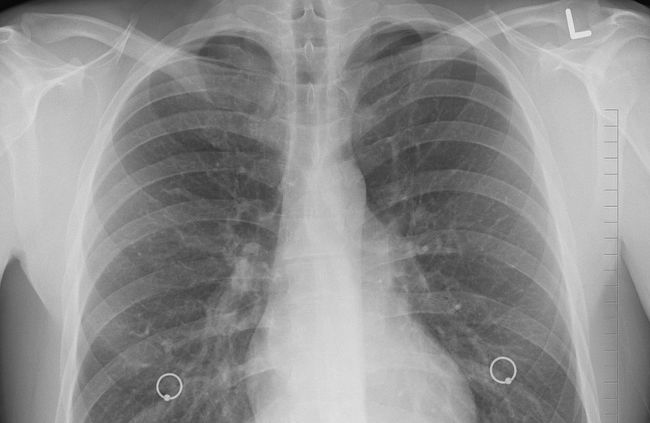

흉부 X선 검사

흉부 X선 검사는 가슴 부위를 촬영하여 폐의 상태를 확인하는 검사입니다. 결핵이 의심될 때 가장 먼저 시행되는 경우가 많으며, 폐에 나타나는 변화 여부를 전체적으로 살펴보는 데 사용됩니다. 촬영 과정은 비교적 짧고 검사 준비가 복잡하지 않아 널리 활용됩니다.

폐에 음영 변화나 비정상적인 그림자가 보이는지 확인할 수 있으며, 결핵과 연관된 소견이 있는지 판단하는 데 참고가 됩니다. 다만 흉부 X선만으로 결핵을 확정할 수는 없고, 감염 여부를 직접 확인하는 검사는 아닙니다. 따라서 흉부 X선 검사는 결핵 가능성을 살펴보는 초기 평가 단계에서 중요한 의미를 가지는 검사 방법으로 설명됩니다.